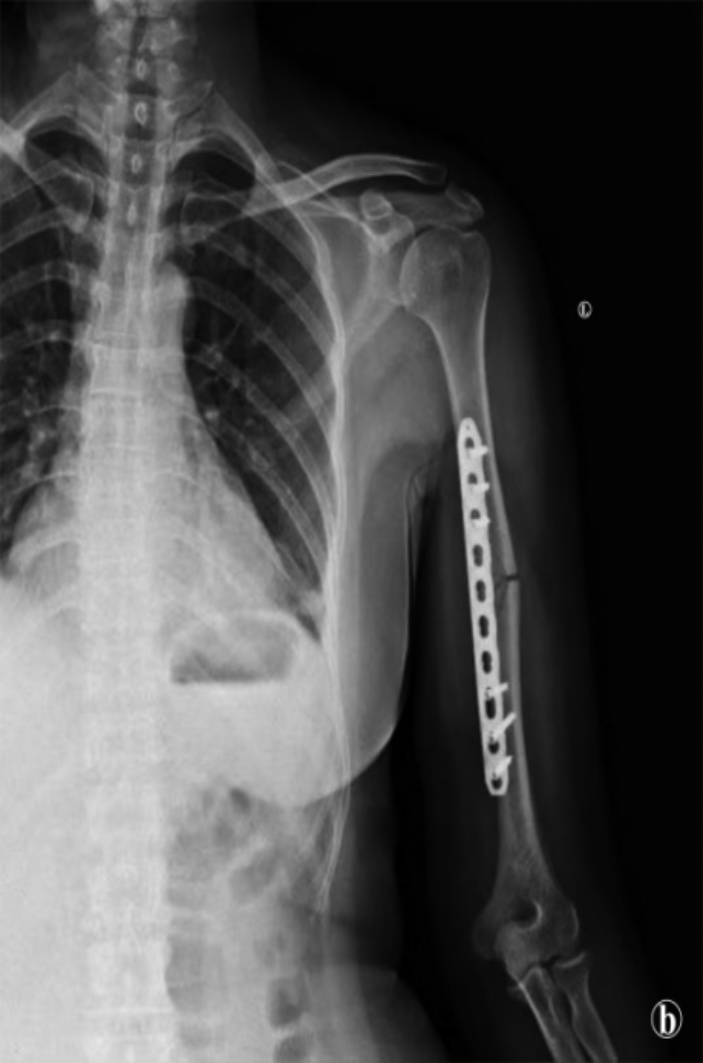

53岁女性,因“摔伤致左上臂肿痛,功能障碍1天”至我院就诊。专科查体:左上臂肿痛,功能障碍,环形压痛,纵轴叩击痛,不能自主活动,手指活动可,肱桡动脉可扪及,左手感觉、血运存在。行X片检查示:左肱骨中段骨折(见图1)。经综合评估患者具体病情并尊重其治疗意愿,我们最终为其选定了前内侧微创入路经皮钢板内固定术作为个体化治疗方案。手术过程:麻醉生效后,患者取仰卧位,术肢常规消毒铺巾,无菌单包扎前臂及手部。以左侧肱骨内髁上约3 cm处作一长约4 cm的纵行切口,作为远端切口;于肱骨近端前侧、三角肌与胸大肌间隙处作一长约5 cm的切口,作为近端切口。依次切开皮肤、皮下组织及深筋膜,沿肱二头肌与肱三头肌间隙(远端)及三角肌、胸大肌与肱二头肌间隙(近端)钝性分离,暴露骨折断端。注意保护走行于肱肌深面的肱动脉、正中神经及肌皮神经。于骨膜表面轻柔剥离,形成贯通远近端的皮下隧道。于远端插入1块10孔肱骨直行锁定钢板,手法复位后依次在骨折远近端置入共六枚锁定螺钉,c臂透视见骨折复位好,内固定稳妥可靠,活动肩关节无受限及撞击。彻底止血,冲洗切口,逐层缝合深筋膜、皮下组织及皮肤,无菌敷料包扎。

Figure 1. Preoperative radiograph demonstrates a midshaft fracture of the left humerus

1. 术前X片示左肱骨中段骨折